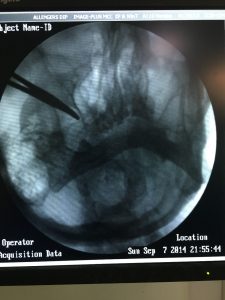

RFA for Trigeminal Neuralgia